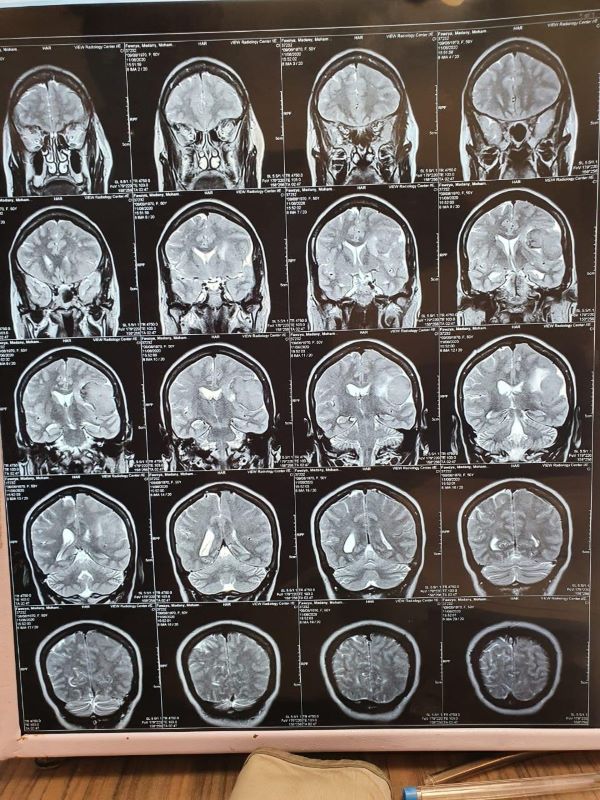

أعلن الدكتور ممدوح مهدى، عميد كلية الطب البشرى بجامعة حلوان، أن الفريق الجراحى المتخصص فى إجراء الجراحات النوعية النادرة؛ نجح فى إستئصال ورم بالمخ من مريضة داخل مستشفى بدر الجامعى التابعة لكلية الطب البشرى بجامعة حلوان.. مشيراً أن المريضة كانت تعانى قبل العملية من أعراض "إرتفاع بضغط المخ، صداع مستمر، غثيان".. مضيفاً أن العملية تعتبر من الجراحات الدقيقة والحرجة فى عالم الطب البشرى.

أضاف عميد كلية الطب البشرى بجامعة حلوان، فى تصريحات خاصة لـ"بوابة الجمهورية" أنه تم عمل جميع  الإجراءات التحضيرية للمريضة قبل العلمية مثل: "الأشعات التحضيرية، التحاليل، الأدوية التحضيرية"، وتم حجزها بالعناية المركزة المجهزة على أحدث المواصفات القياسية العالمية بعد خروجها من غرفة عمليات الكبسولة "ألمانية الصنع" والأحدث من نوعها فى الشرق الأوسط.. كاشفاً أن العملية كانت تحت إشراف د.شريف رسلان أستاذ مساعد جراحة الاعصاب و د.عادل شاكر مدرس التخدير والرعاية الحرجة.

فى ذات السياق، أكد الدكتور إيهاب لطفى، مدير عام مستشفى بدر الجامعى التابعة لكلية الطب البشرى بجامعة حلوان، أن العملية إستغرقت (3) ساعات، وحالة المريضة الان بعد الجراحة مستقرة وتعافت بشكل كامل.. كاشفاً أن جميع مراكز المخ للمريضة تعمل بكفاءة وخرجت من العناية المركزة اليوم وإنتقلت إلى القسم الداخلى "سكن المرضى"، وتستعد للخروج من المستشفى خلال الساعات المقبلة.

ونوه الدكتور إيهاب لطفى، أن الفريق الطبى الذى قام بإجراء العملية الجراحية مكون من: " د. سعيد عيسى مدرس جراحة المخ والأعصاب بطب حلوان،  د. أحمد حامد مدرس مساعد جراحة المخ والأعصاب، د. محمد عباس،  د. حسام أبو سمرة،  د. محمد سليمان،  د. محمد السويسى وجميعهم من قسم جراحة المخ والأعصاب".